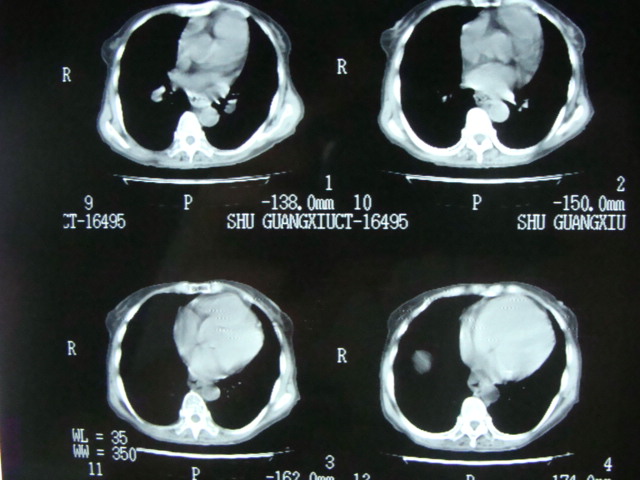

我看食管下段管腔狭窄,壁明显厚,腹水,肝右叶低密度灶

食管癌?肝转移?腹水

建议食管镜检查

考虑:1、肺动脉高压(原因?);

2、肝硬化伴腹水。

3、心脏病变应有听诊,彩超检查。